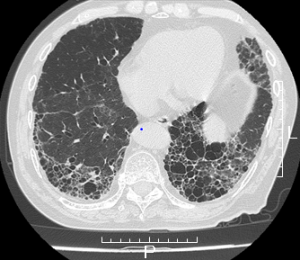

NMC Diagnosis。0b3b59392e9eaf6a38d2ac37cd75fc。間質性肺炎 | 印西そよかぜ内科・呼吸器内科。画像診断 Vol.41 No13. 特集『なぜによくわからない間質性肺炎。「肺炎の画像診断と最新の診療」藤田次郎定価: ¥ 12,540#藤田次郎 #本 #BOOK #健康 #医学